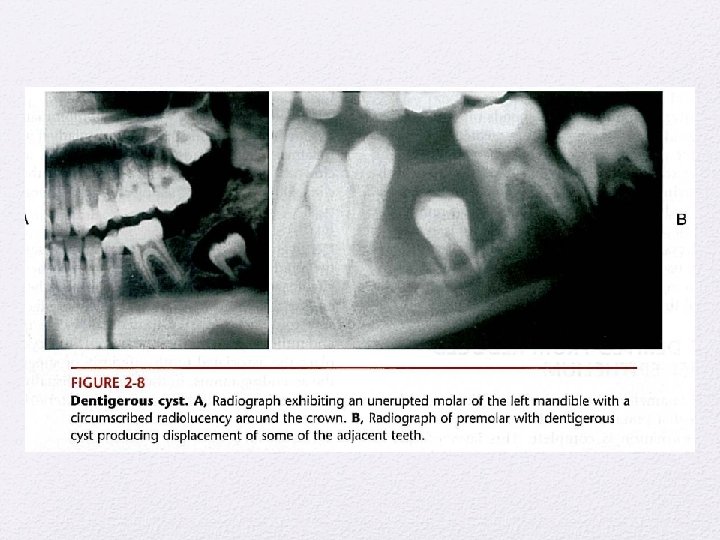

Kista Odontogenik • Kista periapikal • Kista Dentigerous • Kista erupsi • Kist Paradental • Odontogenik keratocyst • Kista lateral periodontal • Kista ginggiva • Kista dental lamina • Kista Glandular odontogenik